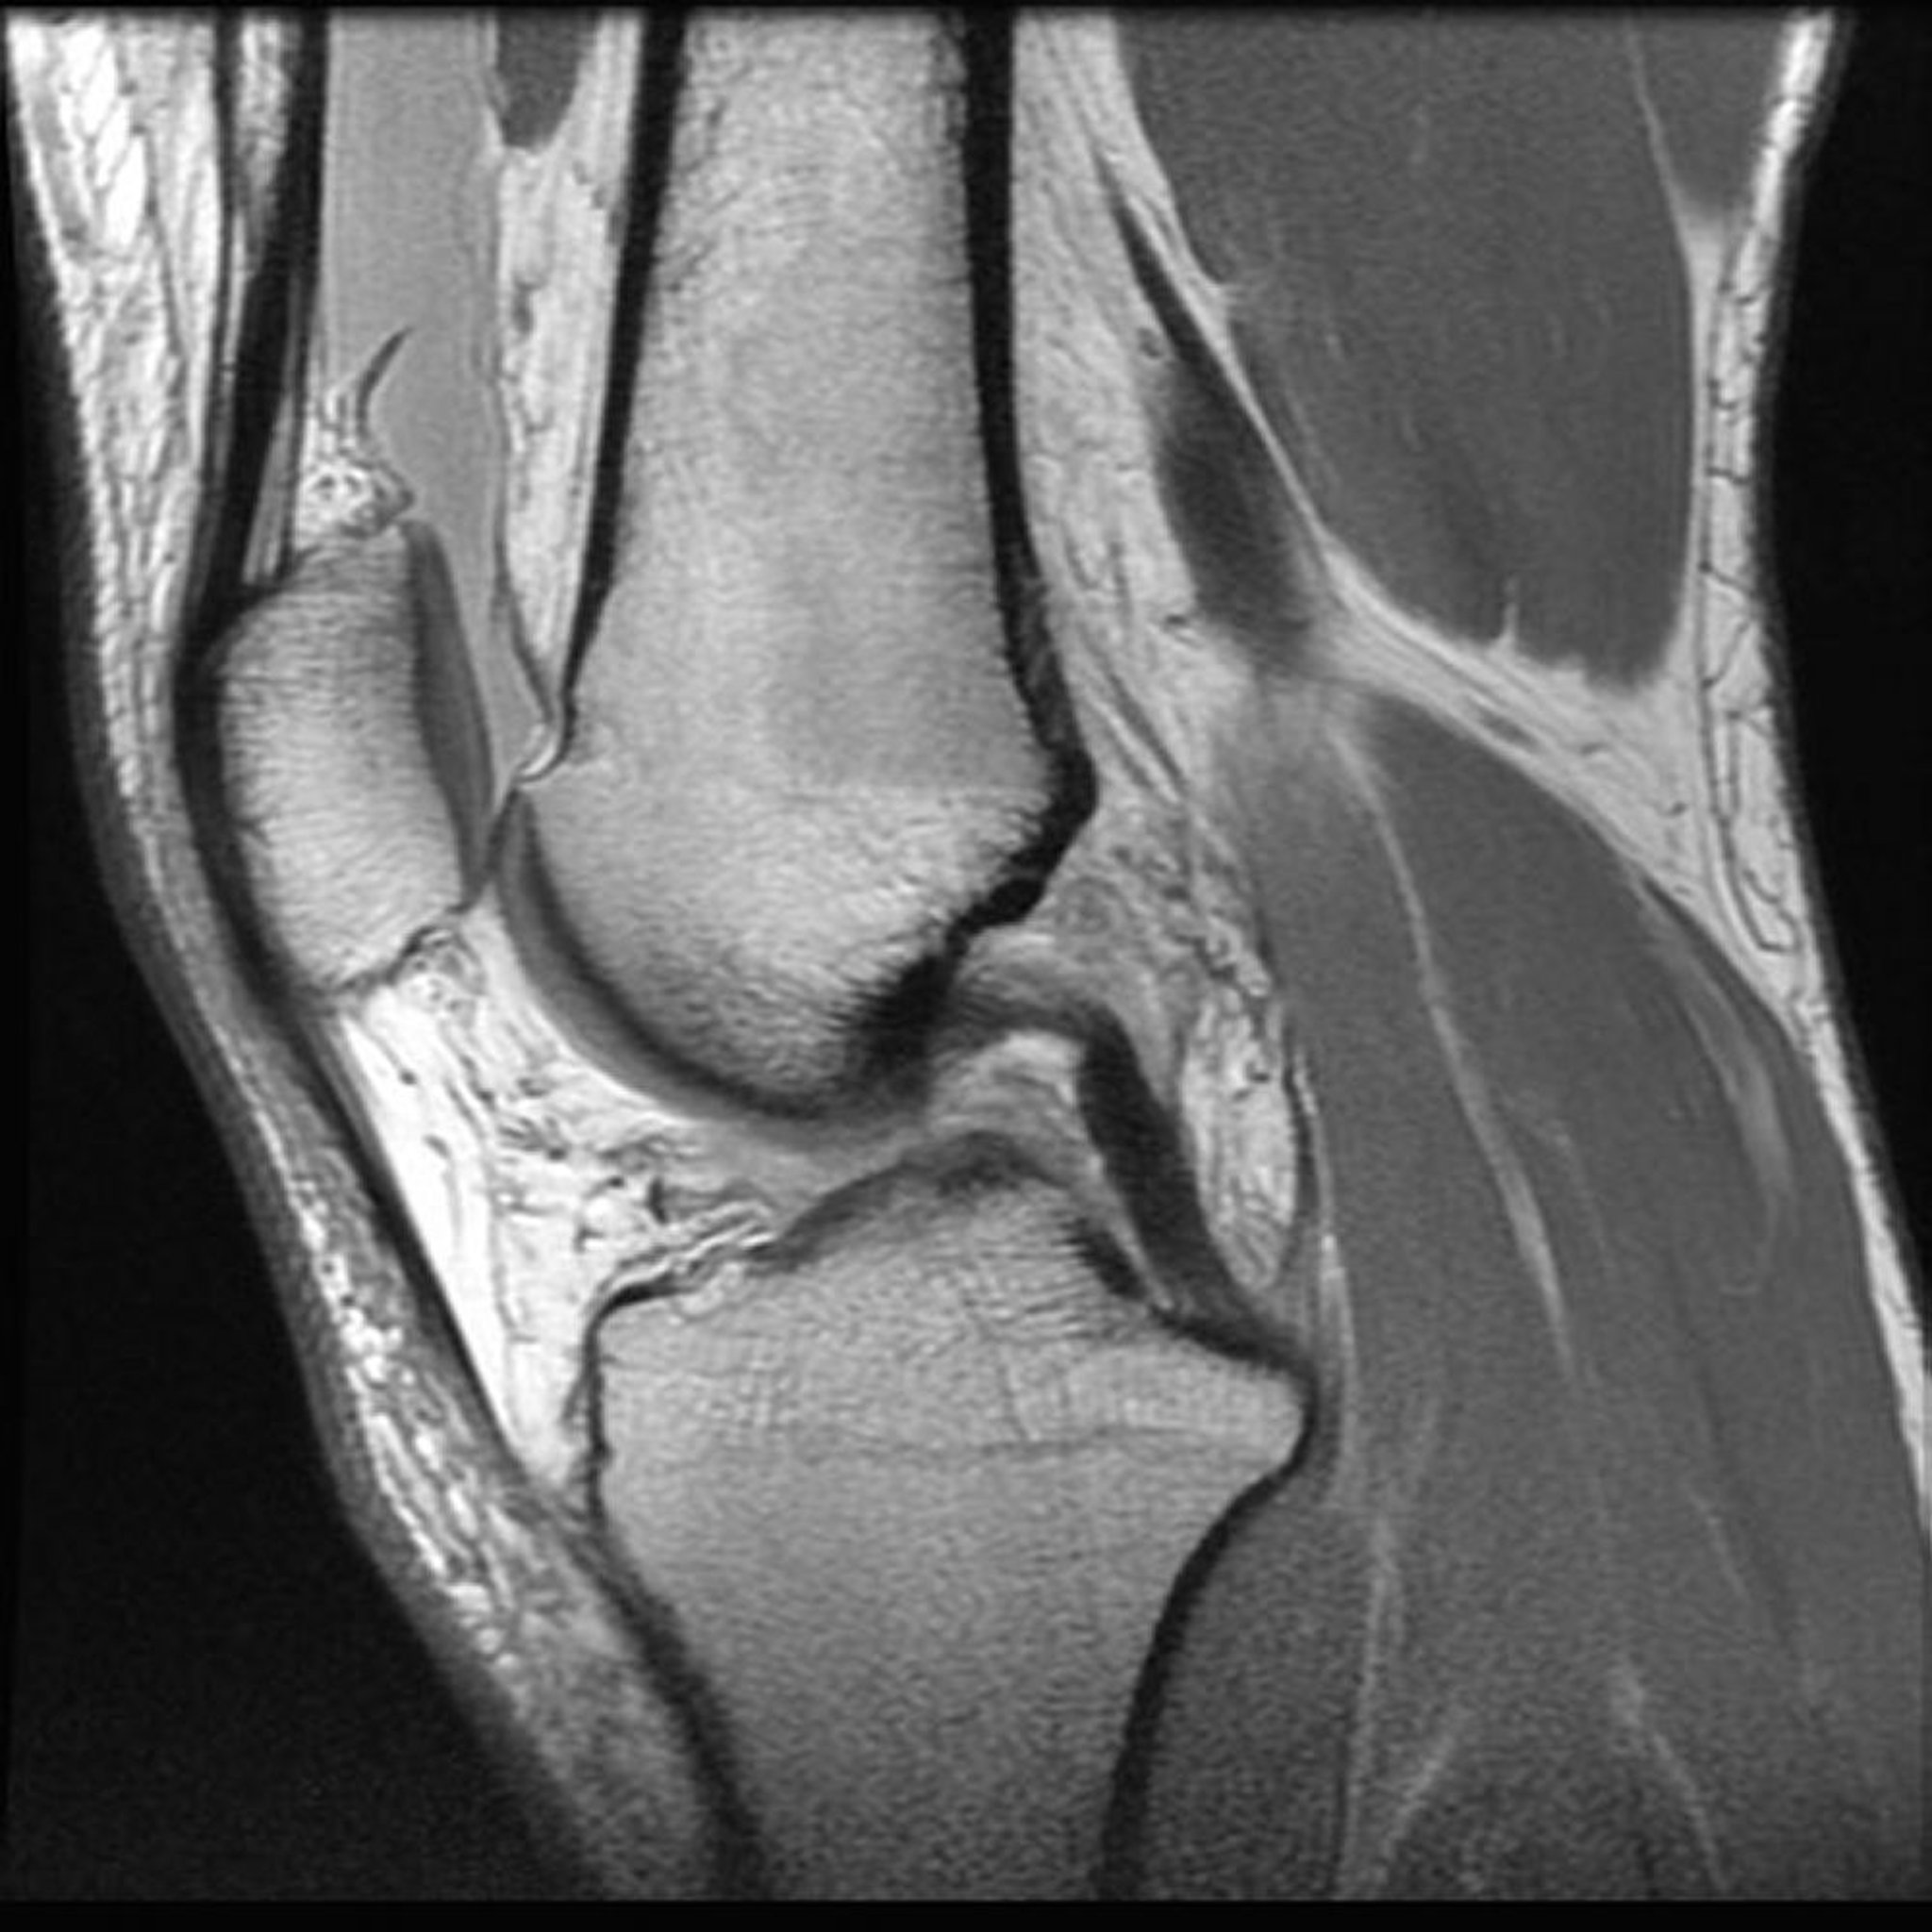

Resonancia magnética nuclear (RMN) de la rodilla

Imagen proporcionada por Jon A Jacobson, MD.